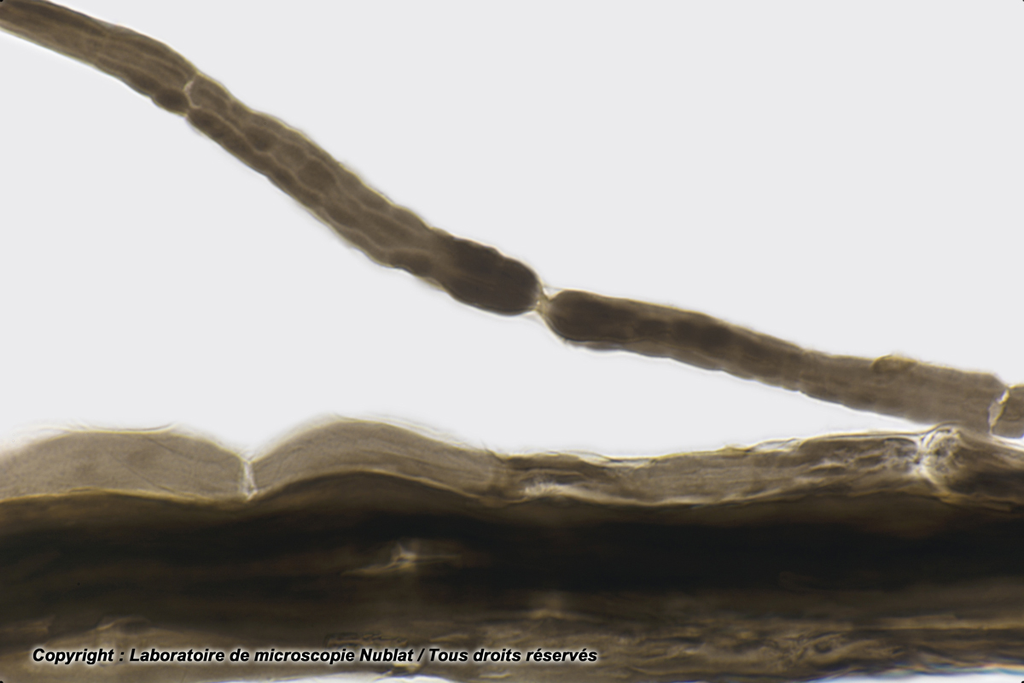

Préparation microscopique Nublat : Nœuds de Ranvier - Fibres nerveuses dissociées AO